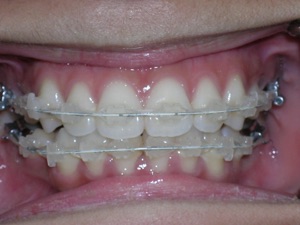

Here are the results.

Hope you like it too!